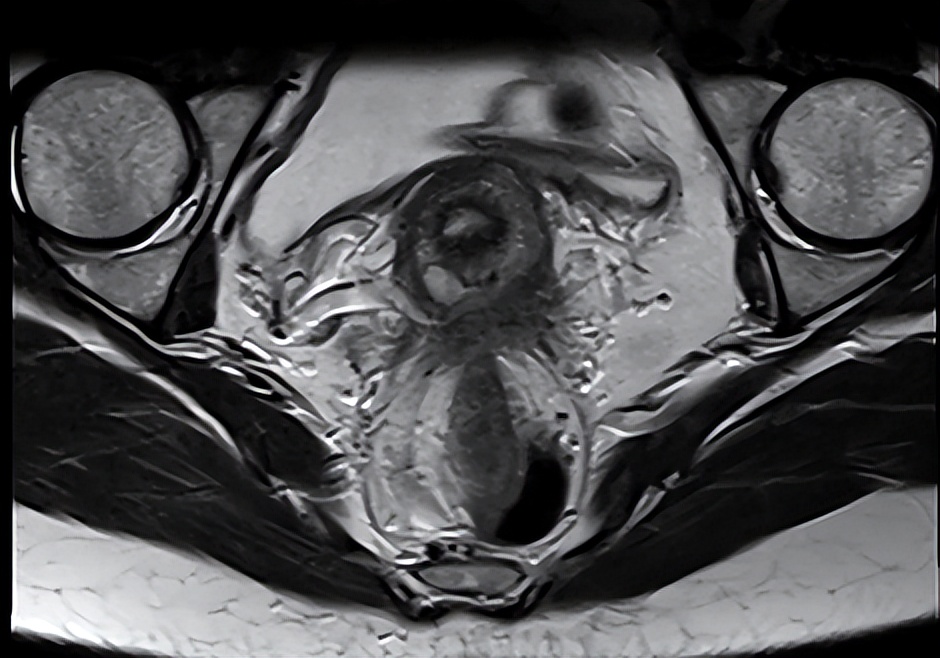

我在给她检查完,发现小腹有突出物初步判断是子宫增大,进一步了解得知温女士每个月经期都会有呕吐,头晕,甚至睡着无法醒来类似昏迷的症状。在进行各项检查后,她的血常规检查显示血红蛋白含量低于70G/L,阴超检测她的子宫均匀增大且子宫肌群回声模糊,不出意外的话就是子宫腺肌症引起的贫血,从而进一步致使头晕昏迷。

子宫腺肌症指的是子宫内膜腺体和间质侵入子宫肌层,导致弥漫或局限性的病变,在一般状态下,子宫内膜是在子宫腔里生长的,当子宫内膜向子宫肌壁间生长,并且浸润生长,而产生一些小的囊区,进而使肌壁增厚,就会出现子宫腺肌症。